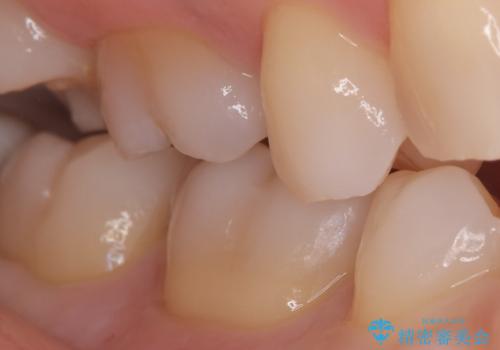

銀歯を丁寧に取り除き、形態を整えた上で、セラミックインレーで修復しました。

当院のセラミックインレーはe-max プレスインレーで製作しています。